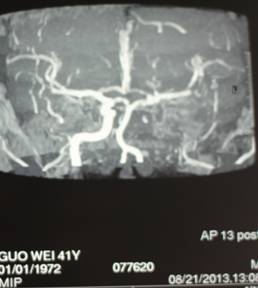

郭某,男,44岁,因口角左歪、言语不清3个月入院治疗。之前在东莞市某医院检查头颅MRA,提示左侧颈内动脉狭窄、闭塞,左侧大脑中动脉远段狭窄、部分闭塞(图一)。

两日后,患者转入广东三九脑科医院,入院时查体:血压147/96mmhg,意识清楚,不完全运动性失语,口角左歪,肌张力正常。DSA影像显示:左侧颈内动脉颈段重度狭窄,左侧大脑中动脉经后交通代偿,其余血管未见明显异常(图二)。

3个月后,患者复查头颅MRI,提示左侧颞后顶叶陈旧性脑梗塞,可能合并有层状坏死(图三),头颈部CTA检查未见异常(图四)。

治疗前MRA(图一) 治疗前DSA(图二)

(图三)

治疗后CTA(图四)